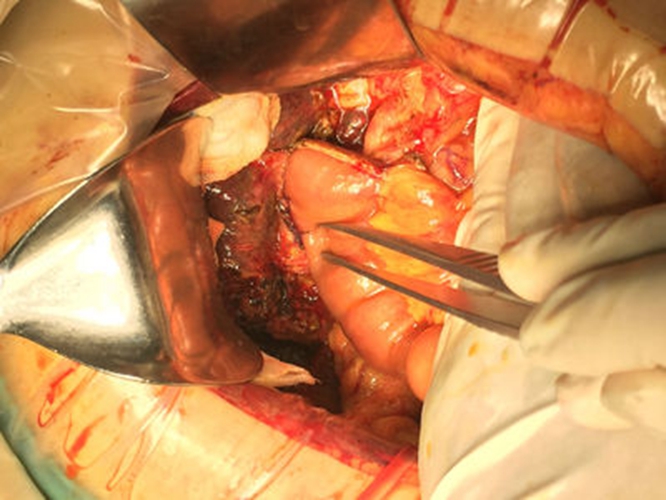

膽管癌圖片

高位膽管癌

肝外膽管癌

肝外膽管癌初晚期

肝外膽管癌黃疸表現